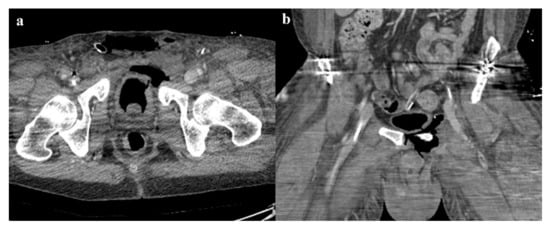

• Grade 2: grade 1 fractures, iliac wing fracture, posterior sacroiliac joint diastasis (Figure 2). Lateral compression grade 2 injuries have a rotational instability and require a stable internal fixation [3]. In these lesions, an adjunctive temporary external fixation is useful [3].

• Zone I: the fracture is located in the sacral wing, lateral to the neuroforamina (Figure 2). In 6% of cases, there is an impingement of L5 or S1 nerve root.

Figure 2. Lateral compression fracture, type 2. Axial CT images show a fracture of both the sacral wings (arrows in (a)), without the involvement of the neuroforamina (zone I). There is also fracture of the iliac wing on the right side (arrow in (b)), and ipsilateral fracture of the superior and inferior pubic branches (arrowheads in (c,d)).